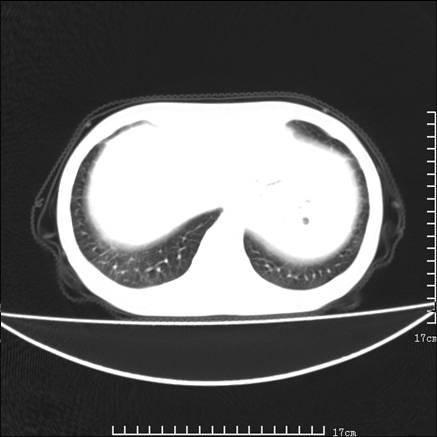

女,46岁,患胃溃疡多年,溃疡大小约1.0cm左右,后于5年前手术,病理为胃癌。主诉:半月前感冒后胸闷,气短,有咳嗽,无明显咳痰,无发热。偶有腰背部不适。

以下为高分辨扫描图像

双肺小叶间增厚,双肺散布粟米影和磨玻璃状影,以双肺上叶为重。结合病史考虑转移(癌性淋巴细管炎)可能性大。

正如caihe主任所言,影像表现结合临床病史应该支持肺癌性淋巴管炎;上肺大片边缘不清的渗出病变,多系感染所致,临床有感冒病史并咳嗽表现。肺癌性淋巴管炎临床一般无咳嗽、咳痰症状。

鉴别:

1、结节病,多位于肺的上中部和后部,呈向心性分布,造成近肺门区的支气管血管束周围间质和胸膜下间质增厚,小叶间隔增厚不明显,即使增厚也较为局限

2、尘肺,可以通过病史,肺外周为主的多发结节,胸膜假斑,聚合成的团块,间质纤维化等鉴别

3、肺水肿,肺水肿可以造成肺间质的增厚,为光滑的增厚且常为双侧对称性分布。